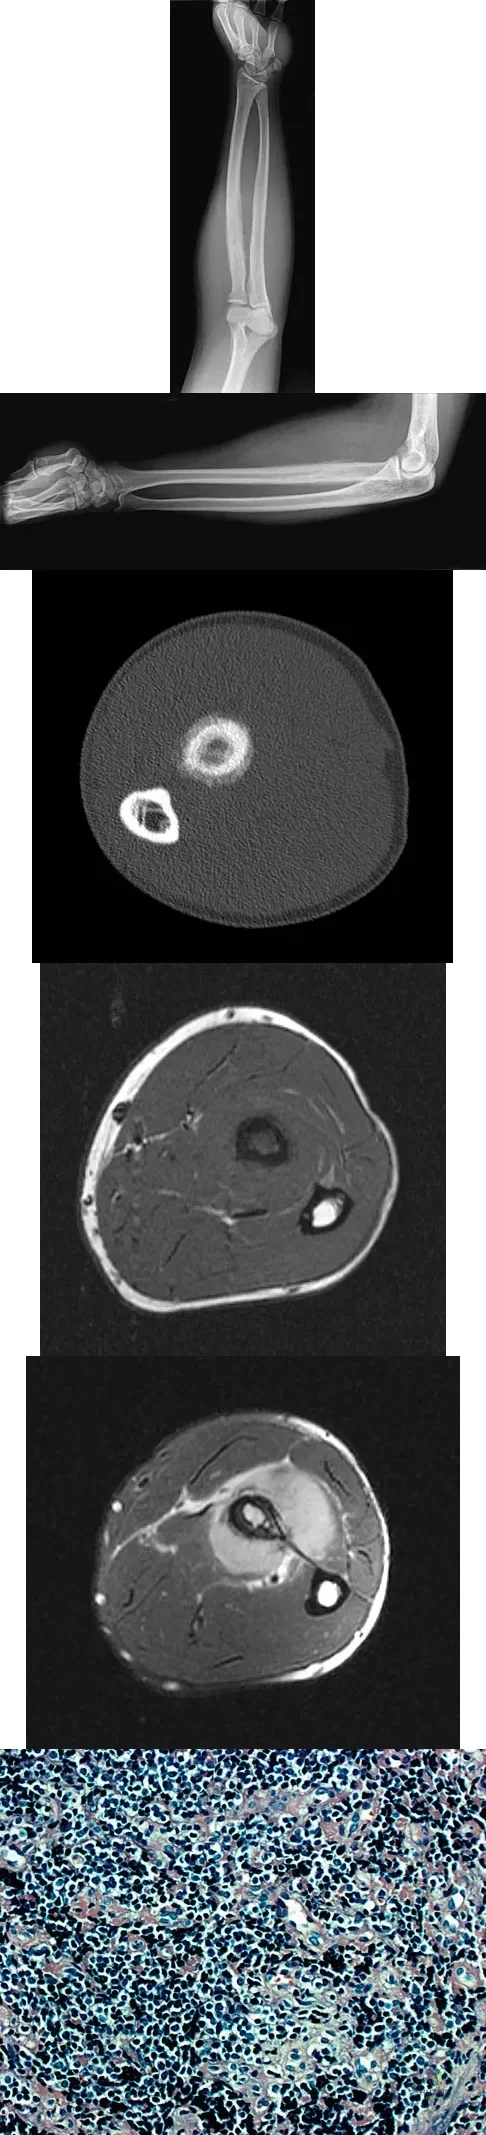

Question 20

A 19-year-old man has had pain and swelling in his left forearm for the past 8 months. Laboratory studies show a mildly elevated WBC count and erythrocyte sedimentation rate. Radiographs are shown in Figures 58a and 58b, a CT scan is shown in Figure 58c, and T1- and T2-weighted MRI scans are shown in Figures 58d and 58e, respectively. A biopsy specimen is shown in Figure 58f. Immunohistochemistry demonstrates that the lesion is negative for leukocyte common antigen (CD34). What is the most common cytogenetic translocation associated with this lesion?

Explanation